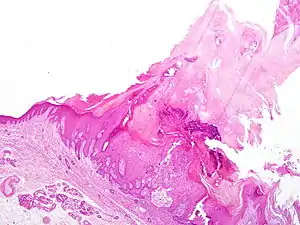

| Actinic keratosis, pre-cancerous area of thick, scaly, or crusty skin (Below) with cutaneous horn tissue (above) |

Cutaneous horn usually arises due to an underlying epidermal lesion, the most common being verruca vulgaris (wart), actinic keratosis (a potentially pre-malignant lesion of dysplastic keratinocytes), or squamous cell carcinoma (a form of skin cancer). These can look essentially identical clinically. The only reliable way to diagnose which type of lesion is present under the horn is to biopsy the lesion and have it microscopically examined by a pathologist (or dermatologist).